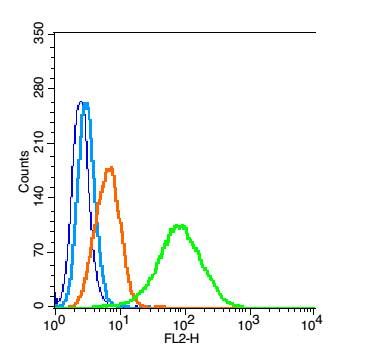

| 产品图片 |  Sample: MDA-MB-231(Human) Cell Lysate at 40 ug Primary: Anti-PALB2 (bs-0588R) at 1/300 dilution Secondary: IRDye800CW Goat Anti-Rabbit IgG at 1/20000 dilution Predicted band size: 131 kD Observed band size: 131 kD  Sample: HepG2(Human) Cell Lysate at 40 ug Primary: Anti-PALB2 (bs-0588R) at 1/300 dilution Secondary: IRDye800CW Goat Anti-Rabbit IgG at 1/20000 dilution Predicted band size: 131 kD Observed band size: 131 kD  Independently Validated Antibody, image provided by Science Direct, badge number 029682:Formalin-fixed and paraffin embedded pig skeletal muscle labeled with Rabbit Anti-PALB2 Polyclonal Antibody, Unconjugated (bs-0588R) at 1:100 for one hour at room temperature followed by conjugation to the secondary antibody Mach2 rabbit HRP-Polymer for 30 min at room temperature and DAB staining.  Independently Validated Antibody, image provided by Science Direct, badge number 029682:Formalin-fixed and paraffin embedded human breast cancer labeled with Rabbit Anti-PALB2 Polyclonal Antibody, Unconjugated (bs-0588R) at 1:100 from one hour at room temperature followed by conjugation to the secondary antibody Mach2 rabbit HRP-Polymer for 30 minutes at room temperature. Positive Control, the staining is correct.  Tissue/cell: human breast carcinoma; 4% Paraformaldehyde-fixed and paraffin-embedded; Antigen retrieval: citrate buffer ( 0.01M, pH 6.0 ), Boiling bathing for 15min; Block endogenous peroxidase by 3% Hydrogen peroxide for 30min; Blocking buffer (normal goat serum,C-0005) at 37℃ for 20 min; Incubation: Anti-PALB2 Polyclonal Antibody, Unconjugated(bs-0588R) 1:200, overnight at 4°C, followed by conjugation to the secondary antibody(SP-0023) and DAB(C-0010) staining  Blank control: Hela(blue), the cells were fixed with 2% paraformaldehyde (10 min) and then permeabilized with ice-cold 90% methanol for 30 min on ice.. Isotype Control Antibody: Rabbit IgG(orange) ; Secondary Antibody: Goat anti-rabbit IgG-FITC(white blue), Dilution: 1:100 in 1 X PBS containing 0.5% BSA ; Primary Antibody Dilution: 1μg in 100 μL1X PBS containing 0.5% BSA(green). |